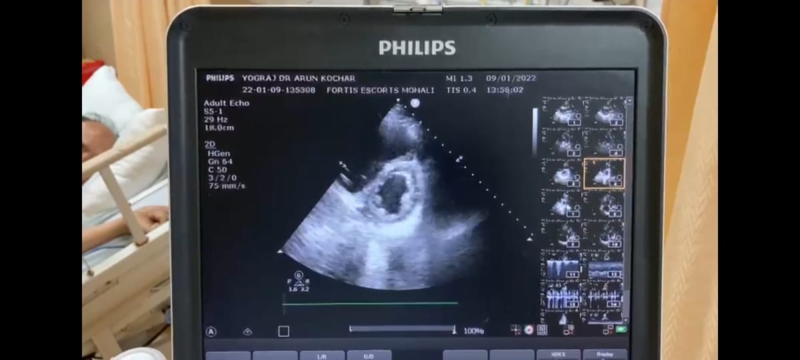

Dr Arun Kochar discusses a case in this article, where a patient with a history of COVID-19 was presented with McConnell's sign. Here he describes how the diagnosis was done that led to the patient's recovery.

McConnell's sign is evidence of acute right ventricular dysfunction observed in patients of acute pulmonary embolism. The test demonstrates evidence of akinesia of mid free right ventricular wall with preserved apical contractility. The test is highly specific and is a very useful rule-in parameter for bedside diagnosis of acute pulmonary embolism.

- His echocardiography revealed evidence of dilated RA and RV with McConnell's sign.

This sign is a distinct echocardiographic feature of acute massive pulmonary embolism. The decision for thrombolysis was made on echocardiography alone. However, for records CT pulmonary angiography was performed, which revealed evidence of massive pulmonary embolism.